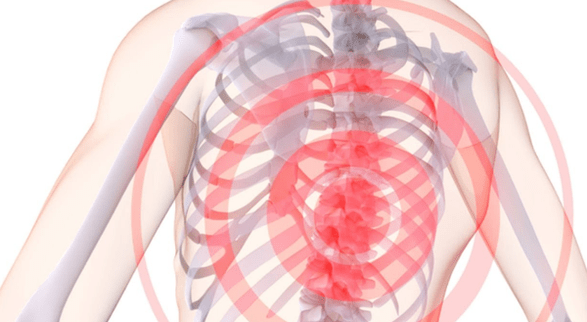

What are the symptoms of thoracic osteochondrosis?First, in case of pain, including:

- interscapular and intercostal neuralgic lumbago;

- pain in the left side of the chest;

- pain in the hands, increasing when they are raised and reaching all the way to the finger;

- pain when bending over;

In addition, thoracic osteochondrosis can be expressed in numbness - not only in the chest, but also in different parts of the body.Sometimes osteochondrosis leads to speech disorders, and sometimes it causes flaky skin, brittle nails, itchy skin and digestive disorders.

Pain with osteochondrosis of the breast can manifest itself in different ways.Sometimes these are mild aches or dull aches that appear in the late afternoon and disappear after physical activity - for example, a short walk.This is usually how the initial stage of thoracic osteochondrosis progresses, when the intervertebral discs are not yet deeply affected.

In the later stages of the development of the disease, pain symptoms often manifest themselves in the form of lumbago.The pain is pronounced, acute, interferes with normal breathing, and unnecessary movements but the situation is getting worse.Often, lumbago begins after a long period of inactivity - for example, several hours of working at a computer in a static position.

What is considered an exacerbation of the disease?This term refers to severe pain.If the patient feels significant discomfort, familiar lumbago and dull pain in the chest area, radiating to the peritoneum, lower back and arms, then it is time to pay maximum attention to your disease.